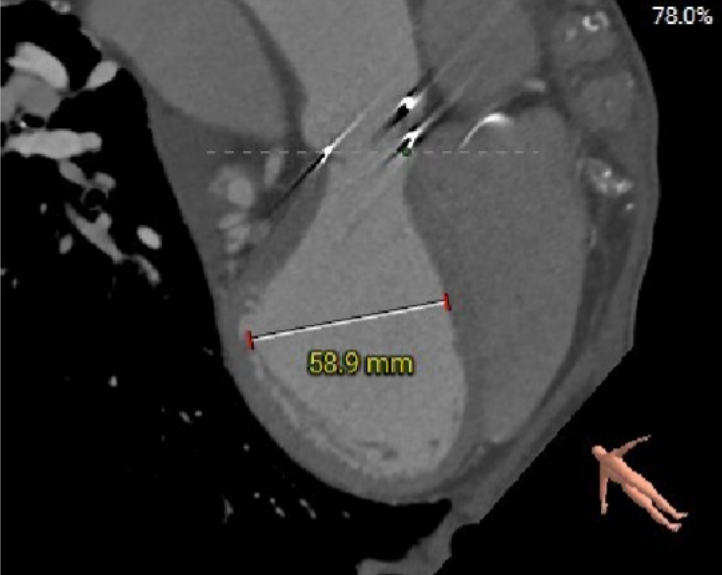

二尖瓣瓣环——内径

二尖瓣瓣环——外径

二尖瓣瓣架高度

选瓣依据:该二尖瓣原置换生物瓣为Hancoke II#31 ,CT测量生物瓣瓣环周长折算直径约28.0mm,瓣架高度约19.1mm;